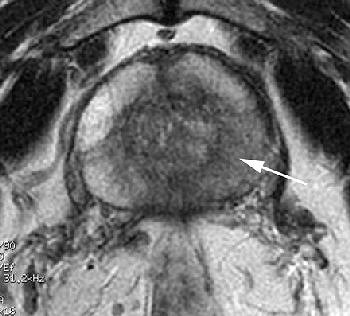

The MRI of the prostate conundrum…helpful or a hoax?